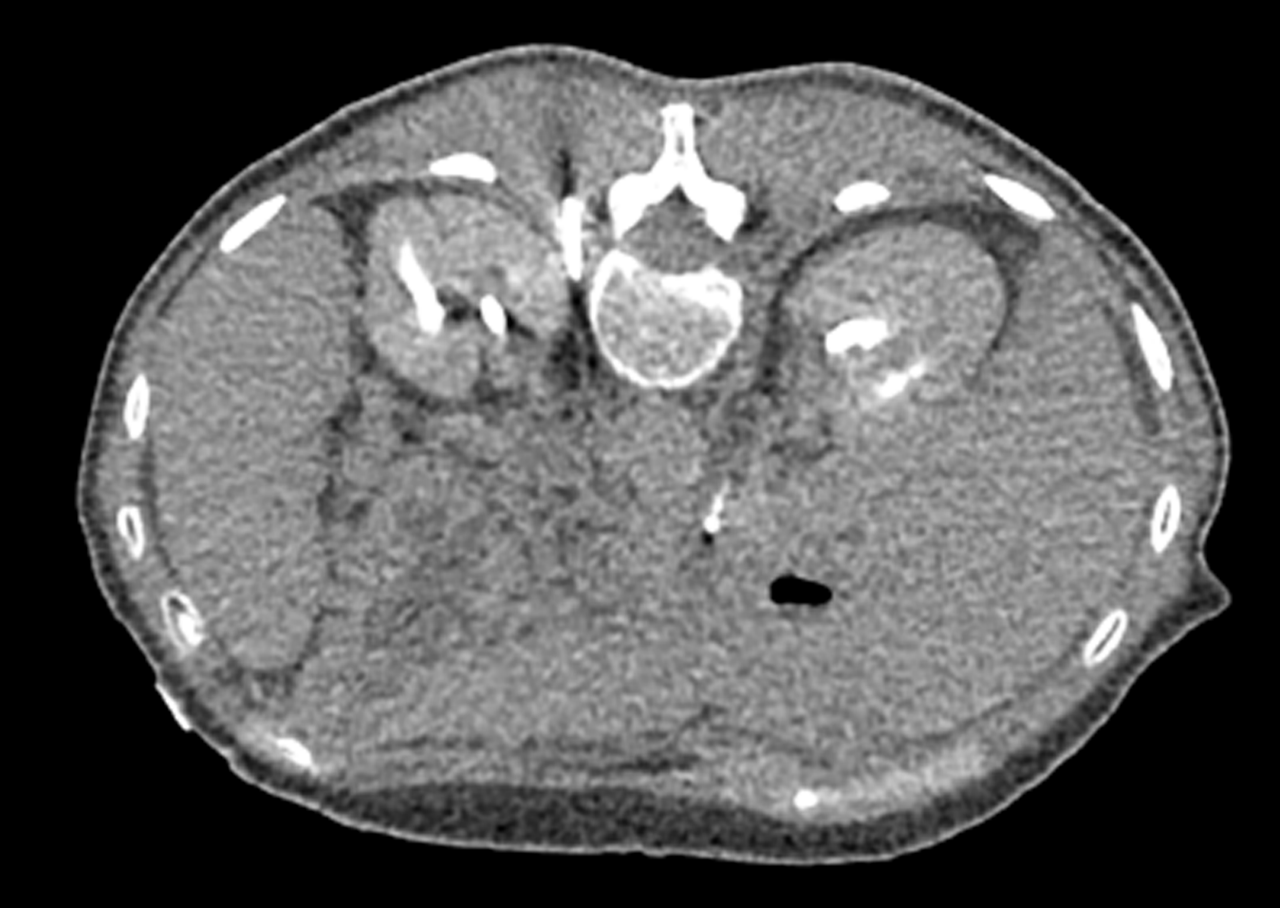

MRI image from Chary cryoneurolysis case MRI image from Chary cryoneurolysis case

Celiac Plexus Cryoneurolysis case study

A 66-year-old man presented with intractable upper abdominal pain refractory to medical management with opiates. MRI axial images through the celiac plexus at the celiac plexus at the level of the celiac axis and SMA origins demonstrate bulky retroperitoneal adenopathy and soft tissue tumor infiltrate. Two IceRod™ 1.5 CX needles were placed within and along the bilateral celiac plexus via CT-guidance. The CT Axial image (right) in prone position shows right-sided iceball formation along the celiac plexus demonstrating excellent coverage. The patient reported pain at 2/10 after a 3-day follow-up pain assessment; the pain score before the procedure was a 10/10.

Aron Chary, MD I MidSouth Imaging - Vascular Interventional Physicians I Memphis, TN